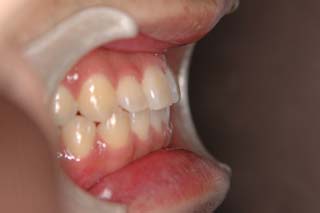

(叢生/顎関節症/上顎左側小臼歯抜歯)

左側の臼歯部干渉が、治療を通じてみられたので、オーバーコレクション気味に軽い臼歯部開咬にしてあります。咬合器上での顎位の偏位はかなり軽減し、頭頚部の症状も随分軽快したようです。歯列の改善と、顎関節症状には、なんだかの関連があると推測されますが、不明なことが多いです。